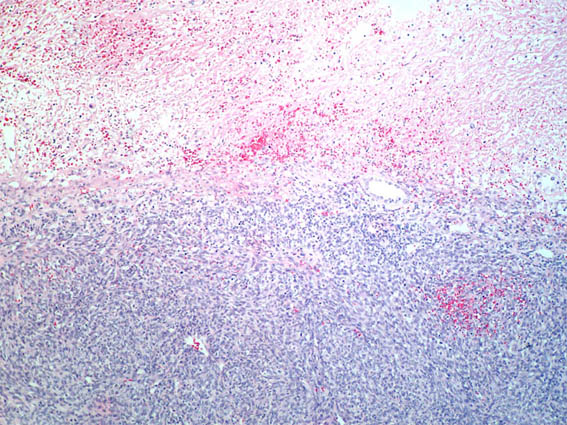

Figure 4. H&E, X100.